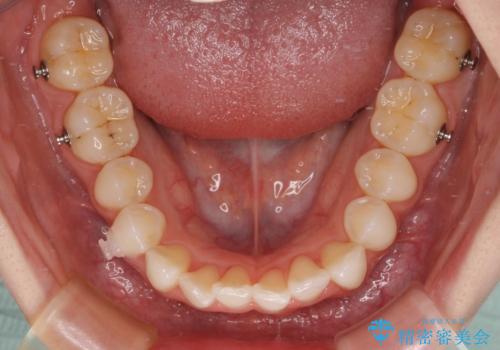

- 前歯のデコボコと下の前歯が隠れてしまう咬み合わせを気にして来院された患者様です。

インビザラインによる上下歯列の拡大と、IPR(歯と歯の間を削る)にるスペースの獲得により、口元のデコボコとディープバイトを改善することとしました。